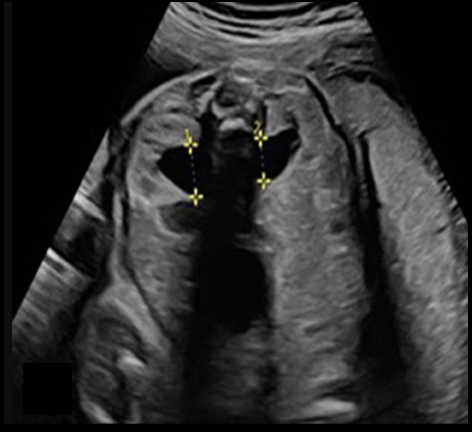

a) dilated urinary bladder

b) cystic hygroma

c) double bubble

d) normal fetal abd/pelvis